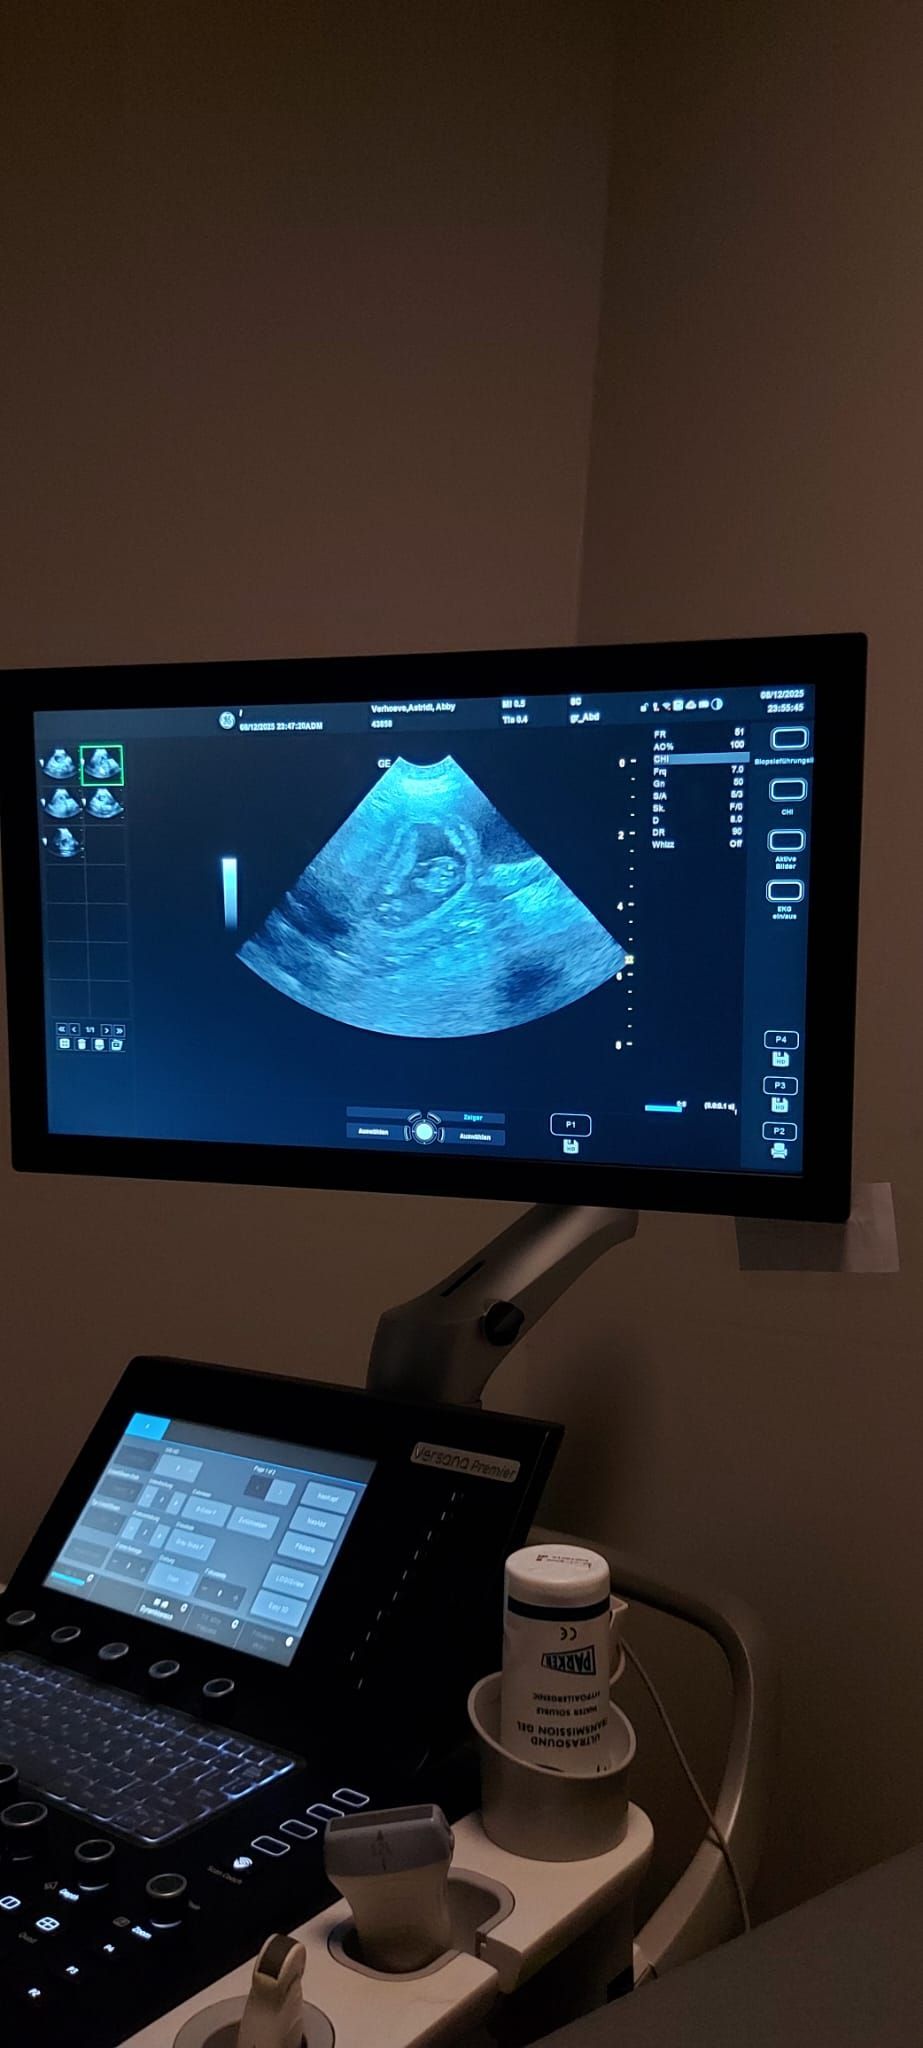

Gestern, genau 31 Tage nach dem Deckakt, stand für unsere Abby ein besonderer Termin an: Wir fuhren zu unserem Tierarzt Dr. med. vet. Andreas Bücheler, um nachzusehen, was sich in ihrem Bauch tut.

Zuerst ging es auf die Waage: Abby hat 550 Gramm zugelegt, was Andreas sofort positiv stimmte. Danach folgte der spannende Teil – der Ultraschall. Abby musste sich dafür auf den Rücken in eine spezielle Halterung legen, was normalerweise gar nicht ihr Ding ist. Doch diesmal überraschte sie uns: Sie legte sich ruhig hin und schaute mich dabei direkt an, als wollte sie sagen: „Na gut, ich mach das jetzt für euch.“

Als Andreas das Ultraschallgerät ansetzte, war seine erste Bemerkung ein fröhliches „Full House!“ 😊. Mit einem Lächeln erklärte er uns, dass da wohl einiges auf uns zukommt. Er prüfte sorgfältig, ob alle Welpen im Bauch gesund aussehen, und bestätigte schließlich: „Das sieht alles sehr gut aus.“

Natürlich hat er uns auch die genaue Zahl verraten – doch die behalten wir noch für uns. Denn bis zur Geburt kann leider noch viel passieren, auch wenn wir alles tun werden, um Abby bestmöglich zu unterstützen.

Wenn alles weiterhin so gut verläuft, dürfen wir uns in der zweiten Januarwoche auf die Ankunft kleiner Kromis freuen. Ein aufregendes Abenteuer beginnt – und wir können es kaum erwarten, die neuen Familienmitglieder willkommen zu heißen.